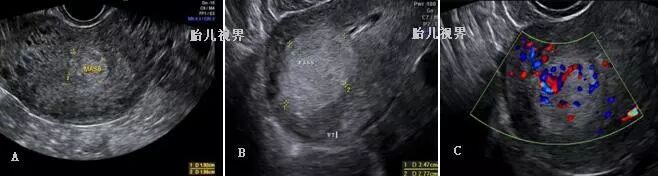

部分性葡萄胎:宫腔内可有妊娠囊结构,囊内可见胚胎或无胚胎,胚胎可存活或死亡,存活胎儿多有畸形或生长受限。胎盘增大,胎盘实质内散在多发囊性结构。部分病例可出现双侧卵巢多房性黄素化囊肿(见图5,6)。部分性葡萄胎早期声像图常不典型,常常于人流后病理检查确诊。

图五、A、B:部分性葡萄胎早期声像,可见孕囊、羊水、甚至胎儿。C:部分性葡萄胎标本[3],可见葡萄状的胎盘和胎儿。D:卵巢黄素化,呈多个囊泡状,直径可达10cm以上。